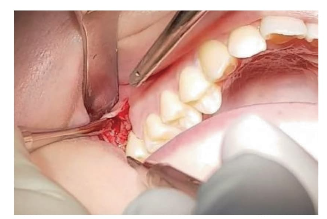

Una planificación adecuada permite seleccionar la técnica quirúrgica más apropiada, desde el diseño del colgajo hasta la necesidad de remover hueso para facilitar la extracción.

En estos casos, la elección del abordaje quirúrgico, el uso de instrumental adecuado y una técnica cuidadosa son determinantes para lograr un resultado exitoso.